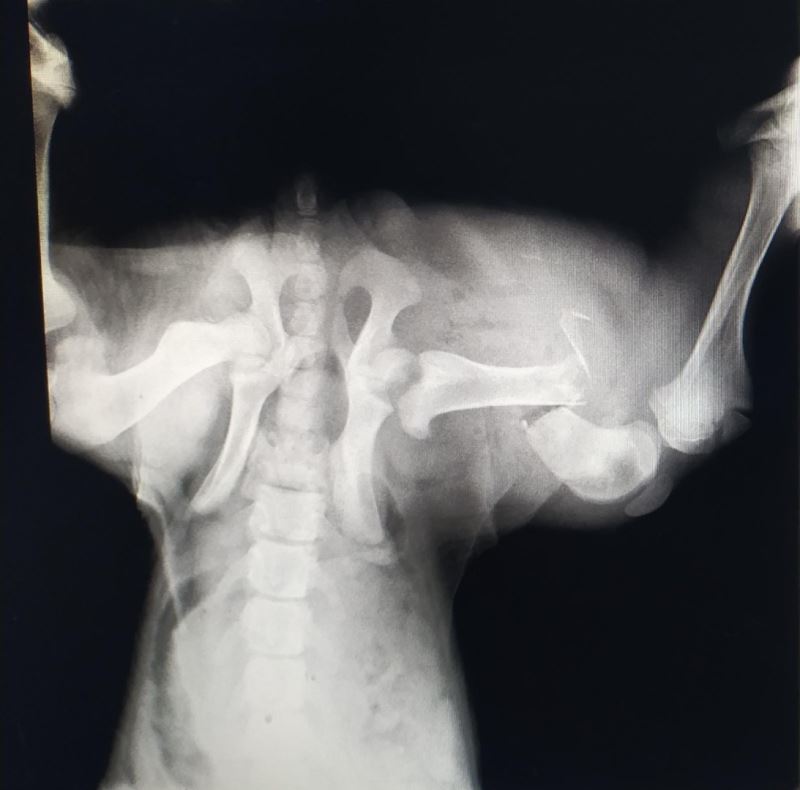

Edinilen bilgiye göre, İzmit’te trafik kazası geçiren sokak köpeği, bir vatandaş tarafından özel veteriner kliniğine götürüldü. Burada köpeğin genel durumunun çok kötü olduğu ve uyutulması gerektiği belirtildi. Ancak vatandaşın vicdanı el vermeyerek, sokak köpeğini Patilik Sokak Hayvanları Kasabasına getirdi. Patilik’te tetkiklerde köpeğin arka bacağında ciddi kırık bulunduğu belirlendi. Bursa Uludağ Üniversitesi Veteriner Fakültesi Cerrahi Anabilim Dalı Bölümünden Prof. Dr. Hakan Salcı’nın gözetiminde uzman hekimler tarafından kan tahlili yapılan ve röntgeni çekilen sokak köpeğinin ayağına plaka takıldı. Sokak köpeğine cerrahi operasyondan sonra ilaç tedavisi de uygulandı.

Patilik’ten yapılan açıklamada, "Patilik Mutlu Sokak Hayvanları Kasabasına getirilen ve arka sağ bacağında kırık bulunan sokak köpeği başarılı bir operasyon geçirerek sağlına kavuştu. Patiliğ’e ilk getirildiğinde hayati verileri çok düşüktü, 6 aylık kangal sokak köpeği Patilik’te tekrar hayat buldu" denildi.